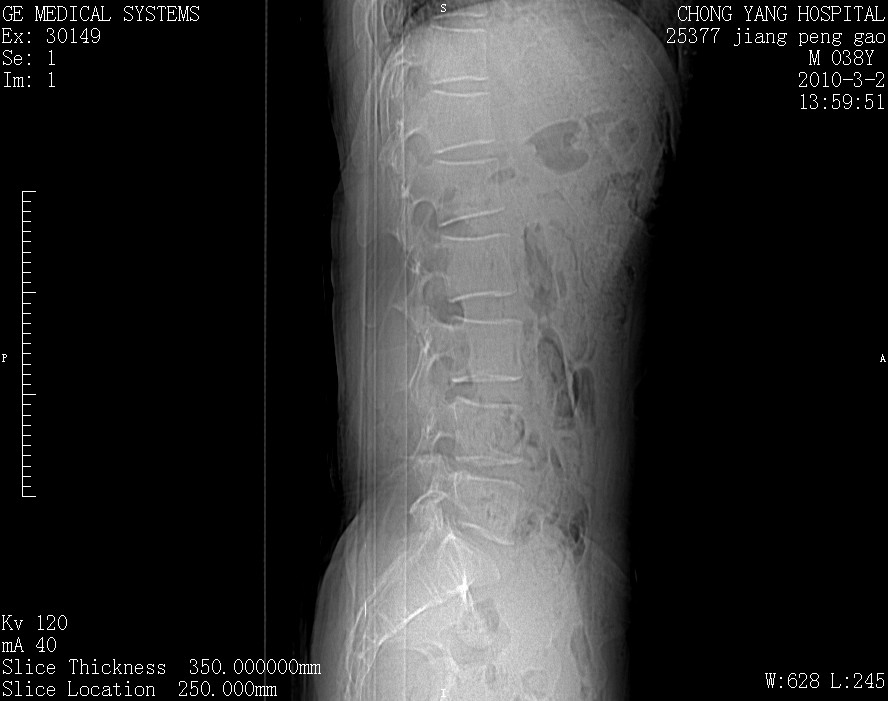

标题: CT24887:M38Y 反复腰痛 无外伤史 未做针灸 竖脊肌为何积气 [打印本页]

标题: CT24887:M38Y 反复腰痛 无外伤史 未做针灸 竖脊肌为何积气

退变,轻度增生/间盘膨出、l5椎后缘软骨结节。

肌间隙积气过多也为退变表现。